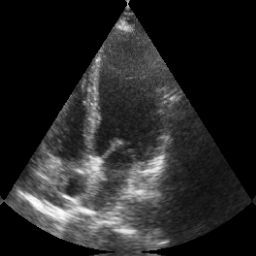

Transthoracic echo is one of the most common means of cardiac studies in the clinical routines. During the echo exam, the sonographer captures a set of standard cross sections (echo views) of the heart. Each 2D echo view cuts through the 3D cardiac geometry via a unique plane. Consequently, different views share some limited information. In this work, we investigate the feasibility of generating a 2D echo view using another view based on adversarial generative models. The objective optimized to train the view-conversion model is based on the ideas introduced by LSGAN, PatchGAN and Conditional GAN (cGAN). The size and length of the left ventricle in the generated target echo view is compared against that of the target ground-truth to assess the validity of the echo view conversion. Results show that there is a correlation of 0.50 between the LV areas and 0.49 between the LV lengths of the generated target frames and the real target frames.